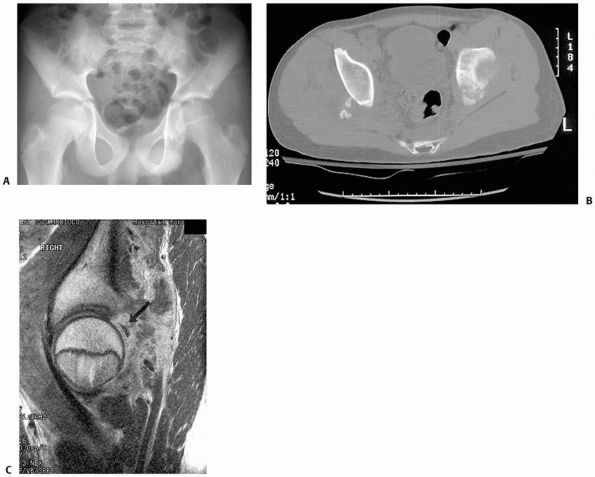

reduction (Fig. 20-26).13

cartilaginous posterior wall fragments in children (Fig. 20-27).

FIGURE 20-26 A. Postreduction anteroposterior pelvis radiograph of a 12-year-old with the left hip appearing nonconcentric. B. CT scan showing a bony fragment from the posterior wall impeding reduction.

FIGURE 20-27 A. Postreduction radiograph of a left hip dislocation in a 12-year-old boy. B. CT scan demonstrates small ossified posterior wall fragments. C. Sagittal MRI demonstrates 90% posterior wall involvement with intra-articular step-off (black arrow).

(From Rubel IF, Kloen P, Potter HG, Helfet DL. MRI assessment of the posterior acetabular wall fracture in traumatic dislocation of the hip in children. Pediatr Radiol 2002;32(6):435-439, with permission.) |